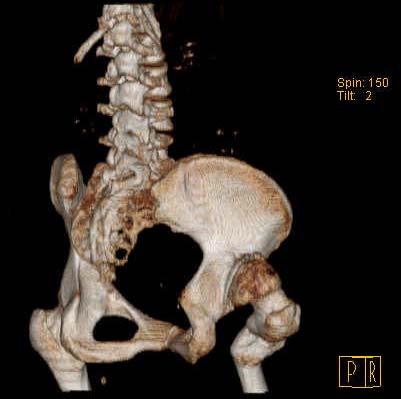

Уважаемые коллеги!Женщина, 35 летВ прошлом по поводу врожденного вывиха бедра перенесла операцию остеотомии по Шанцу

с удлинением правой ноги за счет бедра на уровне диафиза. В последнее время прогрессируют боли в правом тазобедренном суставе, порочное положение правой ноги, затруднена ходьба.Вопросы:1) Целесообразно ли эндопротезирование правого тазобедренного сустава?2) Целесообразный ли следующие действия: канал бедренной кости предполагаем вскрыть для введения ножки протеза на высоте угловой деформации, предполагаем низведение большого вертела с мышцами; протез будет подобран индивидуально, предполагается умеренная версия?В приложении рентгенограммы и трехмерная КТ.В цветном и более качественном варианте КТ размещена здесь

Похожий случай представляем на ретгенограммах. Операция выполнена в 1996 г.